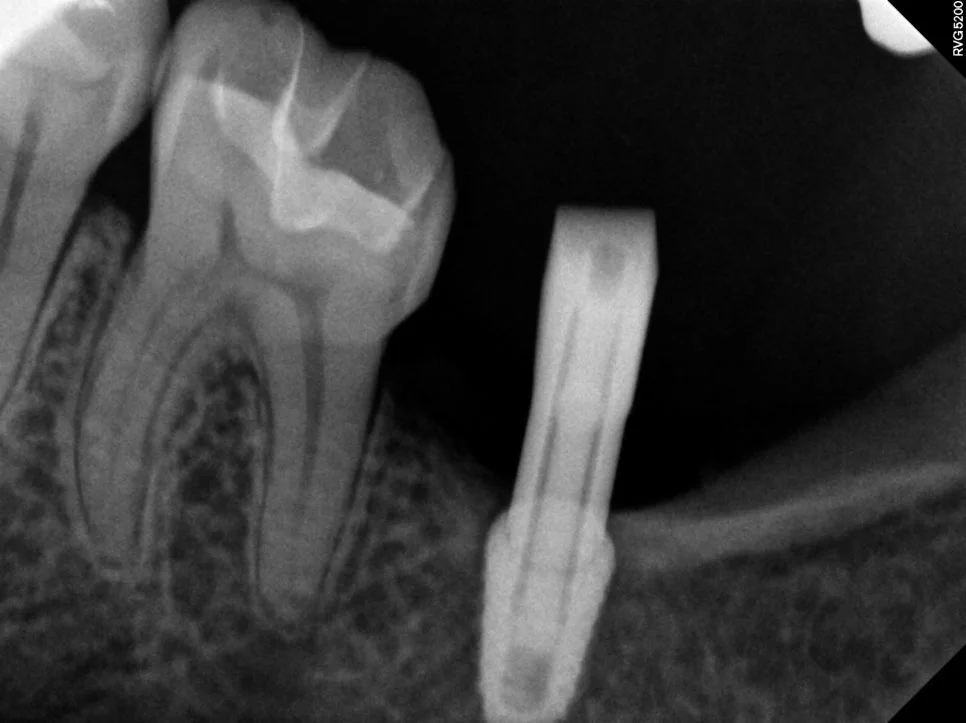

임플란트 틈새 진단 방사선 사진

X-ray에서 임플란트와 치아 사이 틈 확인

사진을 찍어보면 명확하게 임플란트와 치아 사이에 틈이 보이는데요. 이 정도 공간이면 음식물이 정말 엄청나게 끼게 됩니다ㅜ

음식물이 끼는 사이 틈에는 충치/잇몸질환이 둘 다 잘 생기게 되므로 음식물 끼임은 그 자체로 문제입니다ㅜ